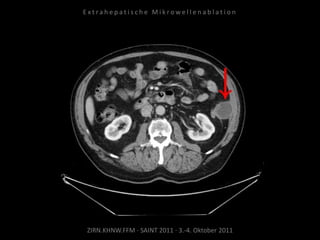

Metastase medial des linken

Musculus iliacus:

1 Nadelposition.